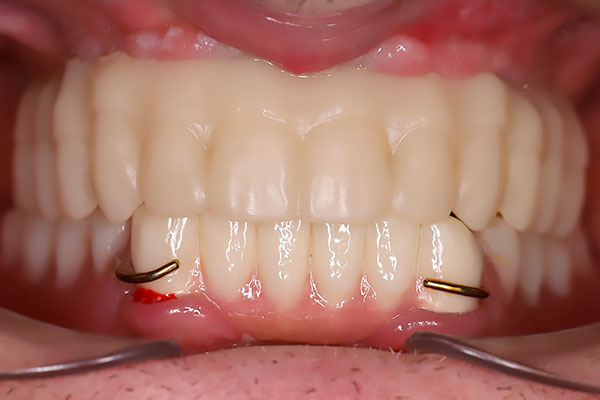

Через 5 дней сняты швы, установлен временный пластмассовый мостовидный протез, проведена коррекция.

Через 4 месяца пациенту установлен постоянный циркониевый мостовидный протез на титановой балке. Состояние костной ткани хорошее. Состояние десны удовлетворительное, жалоб нет.